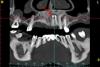

kriokov Опубликовано 8 июля, 2012 Поделиться Опубликовано 8 июля, 2012 немного не в тему, но тоже большая сиська почему не в тему? декомпрессия (марсупиализация) при кистах может применяться, и как метод в комбинации с эндодонтией, так и как метод в комбинации с эндодонтией, и последующим исчерпывающим хирургическим лечением (цистэктомия, цистотомия). Чаще применяется при нагноении кист, при кистах значительного размера.На КТ деструкция кости в обл 22 маленькая, там и без хирургического пособия все благополучно разрешиться может. Ссылка на комментарий

Kivilgar Опубликовано 8 июля, 2012 Поделиться Опубликовано 8 июля, 2012 почему не в тему? декомпрессия (марсупиализация) при кистах может применяться, и как метод в комбинации с эндодонтией, так и как метод в комбинации с эндодонтией, и последующим исчерпывающим хирургическим лечением (цистэктомия, цистотомия). Чаще применяется при нагноении кист, при кистах значительного размера.На КТ деструкция кости в обл 22 маленькая, там и без хирургического пособия все благополучно разрешиться может.Хотелось бы уточнить. Для начала по размерам не маленькой патологии можно предположить, что в канале имелась довольно разнообразная микрофлора, что в свою очередь ухудшает прогноз. Допустим, имеющиеся данные основного и дополнительного методов исследований позволяют предположить об отсутствии внеканальных факторов развития патологии, которые могли бы дополнять и осложнять процесс. В этой ситуации не стоит сразу прибегать к хирургическому вмешательству, которое я бы назвал последним шансом. Если же с самого начала ясно, что киста является истинной и никак не связана с микрофлорой канала, или же неудачу неоднократного консервативного лечения можно связать к примеру с колонией микробов на внешней поверхности корня, то тогда уже во главе угла становятся хирургические методы. То есть необходим дифференцированный и осторожный подход к хирургическому вмешательству с употреблением соответствующих терминов, а не слово киста по поводу и без. Ссылка на комментарий